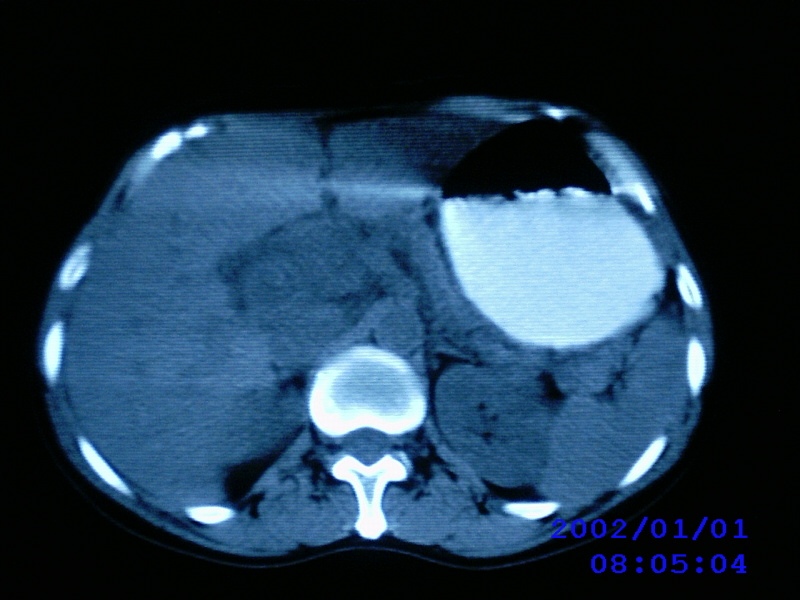

患者,女性,44岁,上腹部疼痛1个多月。b超提示胰头区域有低密度占位性病变。

考虑胰头癌伴肝门腹主动脉旁淋巴转移

老师病人没有黄疸,没有发烧,只是有点畏寒,中上腹部痛,b超提示胰腺没有问题,只是第二肝门近胰头部见一大小约3.7cmx2.5cm椭圆形低回声,形态欠规则,边界可见.

考虑胰头癌并肝门区及腹膜后淋巴结转移。

考虑胰头癌并肝门区及腹膜后淋巴结转移。还是要增强。

胰头及其上部见一类圆性软组织占位,密度欠均匀,胆道系统无扩张,胰头钩突部大小正常,胰管无扩张,十二指肠受压---考虑1 肠道间质瘤,不除外胰头无功能腺瘤。

考虑胰头癌并肝门区及腹膜后淋巴结转移。建议增强。

考虑胰头癌并胰头周围及腹膜后淋巴结转移。